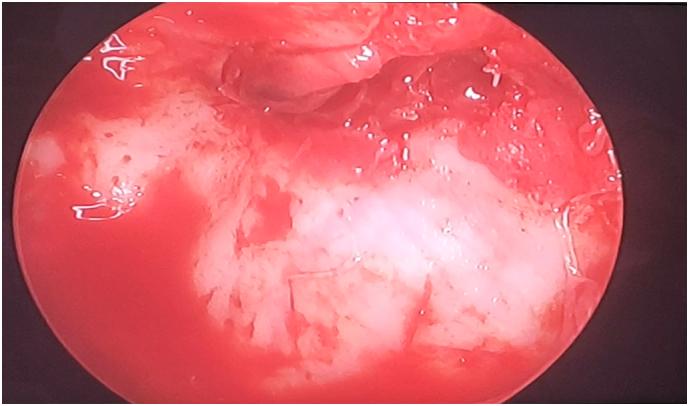

The endoscopy in orbital surgery provides, similar to other surgical fields, the option of combining an extended view of the surgical field with minimally invasive approaches; also allows an excellent functional and esthetic results. Trans-maxillary endoscopy of the orbital floor offers excellent visualization of the posterior bony shelf and confirms that the implant rests securely in place.

In more than 40% of all the facial fractures parts of the orbital rim or/and the internal orbit are injured with a variety of fracture patterns. Accurate assessment is required in order to correct any bone defects or displacements. The surgical approaches have become more reduced offering better control of orbital pathological processes. Orbital lesions are precisely localized through imaging. Also, the approach decision depends on location, size and vascularization. No consensus exists regarding the timing of the repair, the repair technique and the optimal implant. In this case presentation, the defect on the orbital floor was extended by mobilization of the fragments. A combination of incisions was necessary due to the change in the dimensions of the defects intraoperatively and entrapment of orbital tissue by the placement of an implant.